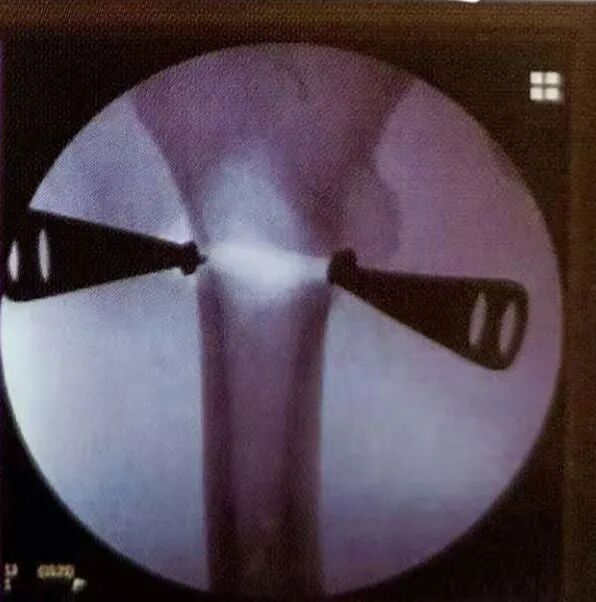

▲准备股骨牵引器在骨折近端的固定针,并通过透视确认固定针的位置安全

A:股骨牵引器安装完成B:通过股骨牵引器进行骨折复位